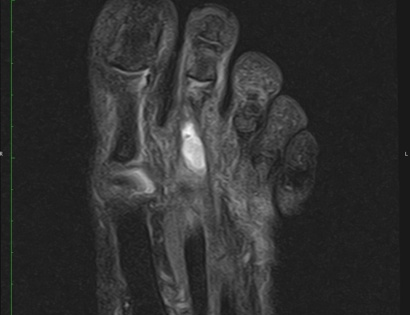

MRI of a Clear Cell Sarcoma

This is an example of a MRI image showing a Clear Cell Sarcoma in the foot.